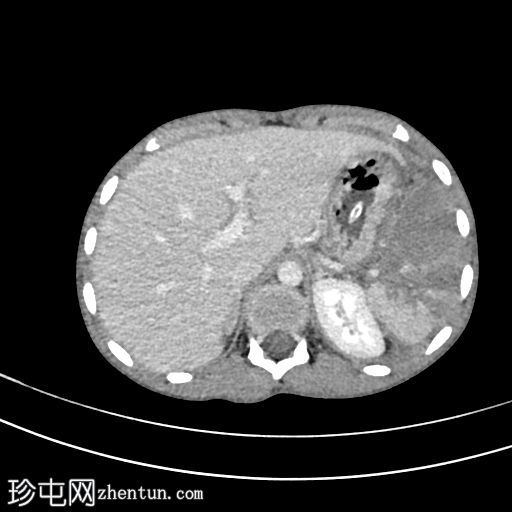

轴位增强扫描(门静脉期)

2.jpg

脾脏显示弥漫性实质损伤(根据美国创伤外科协会(AAST)脾脏损伤分级标准,为IV级损伤)。脾脏实质内可见一灶性造影剂聚集,提示脾内出血而非脾外出血。

腹腔内可见轻度高密度液体,符合血腹表现。

左侧可见轻至中度胸腔积液。

影像学表现符合IV级脾脏损伤。